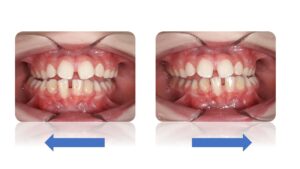

La Classe II Subdivision

La classes II subdivision fonctionnelle est la conséquence d’une mastication préférentielle voir exclusivement unilatérale. Cette dysfonction engendre alors une bascule du plan d’occlusion dans le plan frontal mais également dans le plan vertical et sagittal.

L’orthodontie systémique permet d’appréhender cette pathologie par l’analyse des latéralités mandibulaires (AFMP).

Le traitement qui en découle est donc fonctionnel et stable car il permet une réorientation du plan occlusal, symétrisant ainsi les AFMP et donc la mastication.

C’est donc la fonction qui joue le rôle de contention des traitements systémiques.